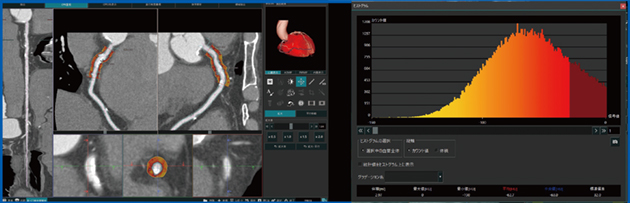

Abierto Visionを用いて心外膜脂肪解析を行ったところ,脂肪組織の体積がわずか2〜3分で簡便に算出された。FAIの画像も数分で表示でき(図5 左),ヒストグラム解析も行えるため(図5 右),CT値の平均値はもとより,将来的にはCT値のバラツキも指標として役立てられるようになると考えている。

図5 心臓CT解析におけるFAIの画像(左)とヒストグラム解析(右)